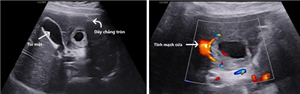

Thai lạc chỗ ở gan (TOG) là một thể không thường gặp của thai trong ổ bụng (TTOB)

Xem thêm